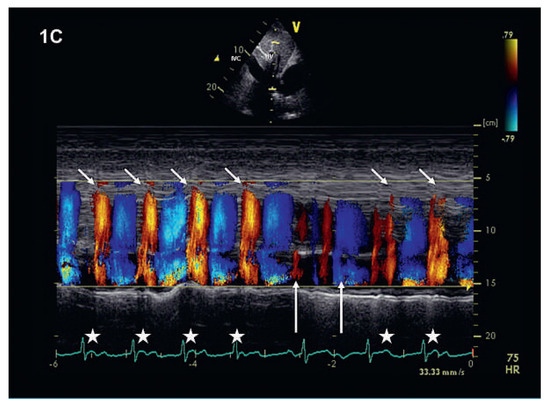

A 59-year-old man with severe mitral regurgitation underwent successful mitral valve repair. Postoperative recovery was uneventful except for the development of a third-degree atrio-ventricular block (fig. 1A). The haemodynamic consequences of the atrio-ventricular dissociation were observed during echocardiography (fig. 1B and fig. 1C): at the beginning and the end of the re- cordings, right atrial depolarisation and contraction occurs during ventricular systole when the tricuspid valve is closed, leading to reversal of blood flow (short arrows). This echocardiographic finding represents the clinically observable jugular venous pulsation called “Cannon waves”. In contrast, when the atrio-ventricular sequence is more or less correct, the backflow into the IVC and the HV is minimal (long arrows).

Figure 1C. Colour-Doppler M-inode through a hepatic vein confirming the findings from Figure 1B.